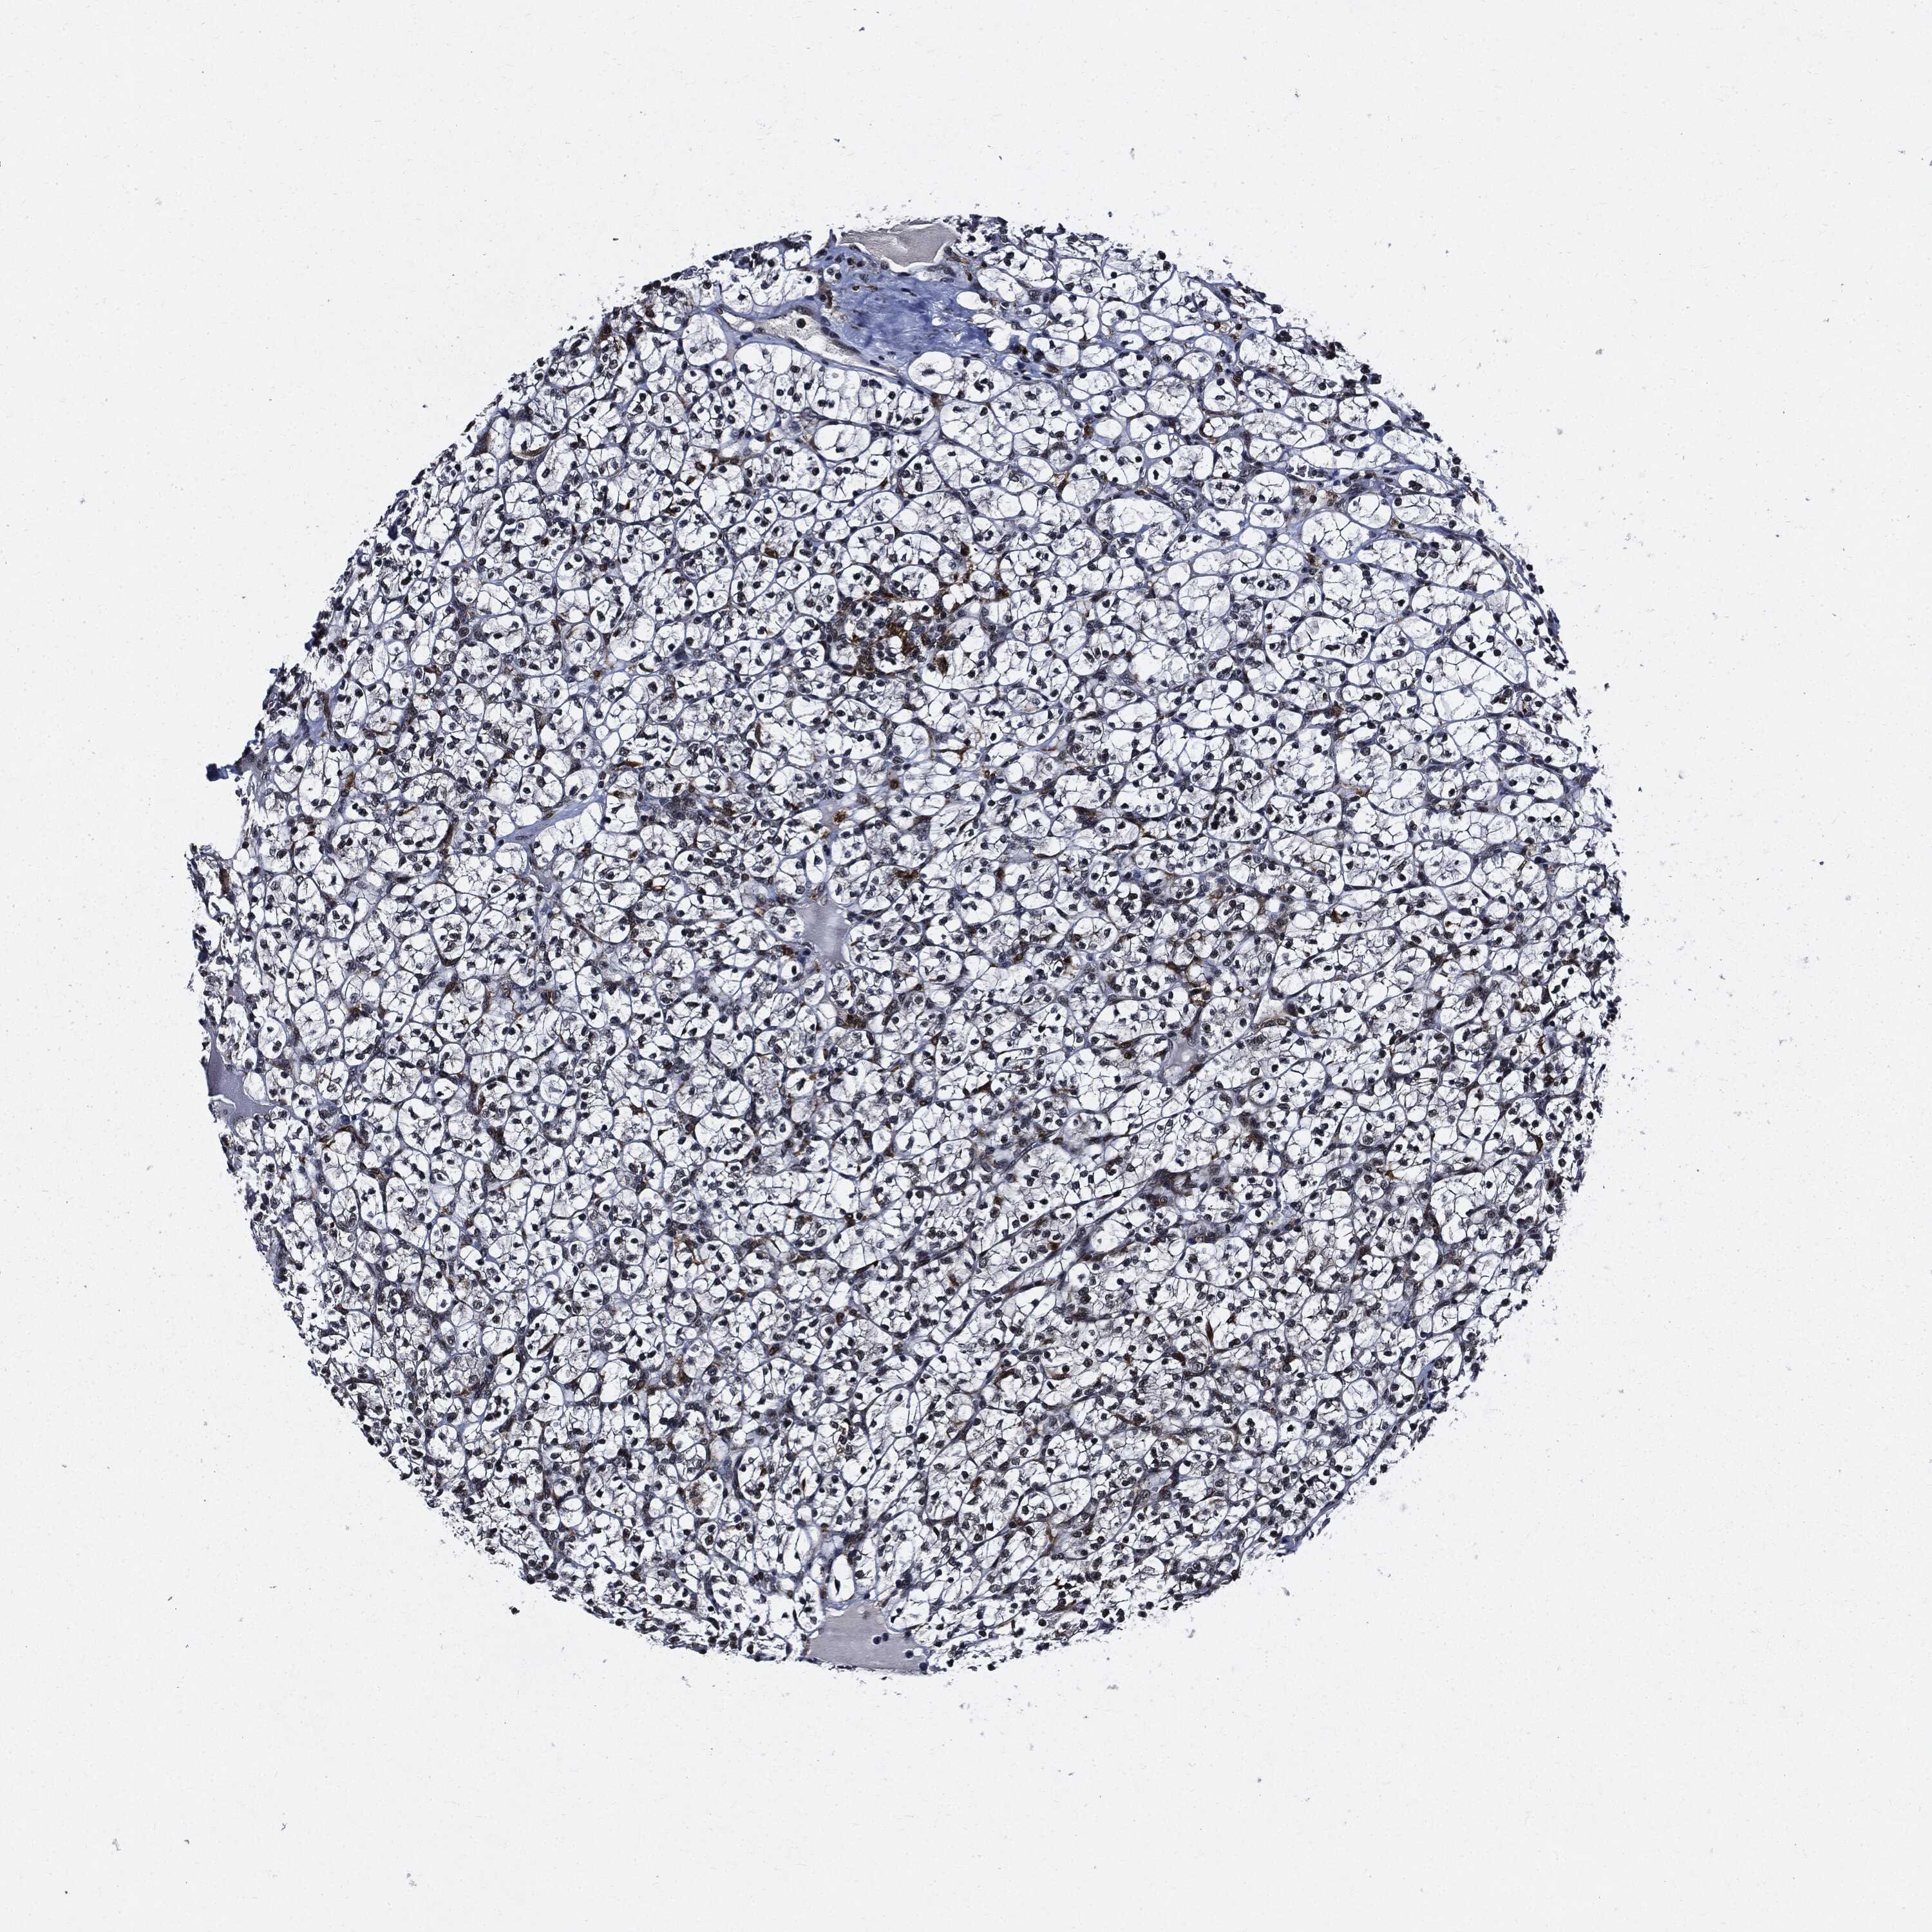

KIDNEY RENAL CLEAR CELL CARCINOMA (TCGA) - Interactive survival scatter ploti

The Survival Scatter plot shows the clinical status (i.e. dead or alive) for all individuals in the patient cohort, based on the same data that underlies the corresponding Kaplan-Meier plots. Patients that are alive at last time for follow-up are shown in blue and patients who have died during the study are shown in red.

The x-axis shows the expression levels (FPKM) of the investigated gene in the tumor tissue at the time of diagnosis. The y-axis shows the follow-up time after diagnosis (years). Both axes are complimented with kernel density curves demonstrating the data density over the axes. The top density plot shows the expression levels (FPKM) distribution among dead (red) and alive patients (blue). The right density plot shows the data density of the survived years of dead patients with high and low expression levels respectively, stratified using the cutoff indicated by the vertical dashed line through the Survival Scatter plot. This cutoff is automatically defined based on the FPKM cutoff that minimizes the p-score. The cutoff can be changed by dragging the vertical line or by entering a cutoff value in the square labeled "Current cut-off".

Under the Survival Scatter plot the p-score landscape (black curve; left axis) is shown together with dead median separation (red curve; right axis). Dead median separation is the difference in median mRNA expression between patients who have died with high and low expression, respectively. It is calculated as follows: median FPKM expression of dead patients with high expression - median FPKM expression of dead patients with low expression. This is intended to aid the user in visually exploring custom cutoffs and the associated p-scores and dead median separation.

Individual patient data is displayed and can be filtered by clicking on one or more of the category buttons on the top of the page. Categories describing expression level and patient information include: high, low, alive, dead, female, male and tumor stages. The scale of the x-axis can be toggled between linear and log-scale by clicking on the "x log" button. Mouse-over function shows TCGA ID, patient information and mRNA expression (FPKM) for each patient.

& Survival analysisi

Kaplan-Meier plots summarize results from analysis of correlation between mRNA expression level and patient survival. Patients were divided based on level of expression into one of the two groups "low" (under cut off) or "high" (over cut off). X-axis shows time for survival (years) and y-axis shows the probability of survival, where 1.0 corresponds to 100 percent.

SUGT1 is potential prognostic, high expression is favorable in Kidney Renal Clear Cell Carcinoma (TCGA)

Best expression cut offi

Based on the FPKM value of each gene, patients were classified into two groups and association between prognosis (survival) and gene expression (FPKM) was examined. The best expression cut-off refers the FPKM value that yields maximal difference with regard to survival between the two groups at the lowest log-rank P-value. Best expression cut-off was selected based on survival analysis .

When clicking on this number, the vertical dashed line indicating cut-off, the interactive survival plot, and the Kaplan-Meier curve will be adjusted to show results based on the best expression cut-off.

: 37.63

Median expressioni

Median expression refers to the median FPKM value calculated based on the gene expression (FPKM) data from all patients in this dataset. When clicking on this number, the vertical dashed line indicating cut-off, the interactive survival plot, and the Kaplan-Meier curve will be adjusted to show results based on the median expression.

: N/A

Median follow up timei

Median follow up time refers to the median time (years) after diagnosis with this type of cancer, based on clinical data from all patients in this dataset.

P scorei

Log-rank P value for Kaplan-Meier plot showing results from analysis of correlation between mRNA expression level and patient survival.

N/A

5-year survival highi

5-year survival for patients with higher expression than the expression cutoff.

For melanoma and glioma, 3-year survival is shown.

5-year survival lowi

5-year survival for patients with lower expression than the expression cutoff.

TCGA RNA samplesi

RNA-seq data is reported as average FPKM (number Fragments Per Kilobase of exon per Million reads), generated by the The Cancer Genome Atlas (TCGA) .

Normal distribution across the dataset is visualized with box plots, shown as median and 25th and 75th percentiles. Points are displayed as outliers if they are above or below 1.5 times the interquartile range. FPKM values of the individual samples are presented next to the box plot.

Average pTPM 37.5

Number of samples 521